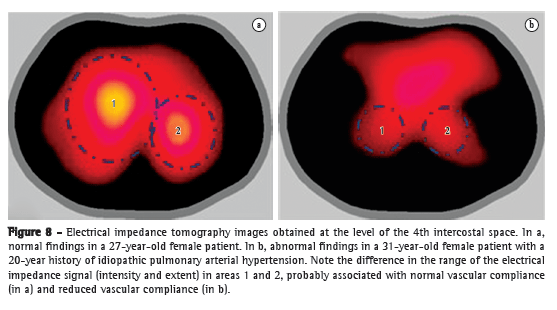

Having been widely studied, CT angiography has gained significant ground in the evaluation of acute PTE, becoming as accurate as pulmonary angiography but without its invasive nature. Some authors consider CT angiography to be the diagnostic imaging method of choice in the assessment of acute PTE.(34-36) This is explained by the various advantages of CT angiography: its high resolution allows the visualization of arteries and filling defects up to the distal portion of the pulmonary vasculature, reaching subsegmental vessels of 2-3 mm (Figure 6); it has excellent interobserver agreement, far superior to that of scintigraphy; its sensitivity is so high that a negative test result allows the safe discontinuation of anticoagulation therapy.(37) One must be alert, however, to the dangers inherent in the method. Technical or pathophysiological factors might lead to the interpretation of pseudo-filling defects, providing false-positive results. The possibility of motion artifacts in patients with tachypnea should be taken into consideration, as should the time interval between contrast injection and image acquisition, as well as the occurrence of hypoxic pulmonary vasoconstriction in poorly aerated regions. The advent of 64-channel scanners created another danger: the possibility of an excessive number of false-positive results. However, that possibility was ruled out in a recent study.(38)

An excellent model of disease in the pulmonary microcirculation is PAH, in which vascular remodeling directly affects the distensibility properties of microcirculation. When vascular compliance is reduced, with consequent accommodation of lower volumes, the electrical impedance change in PH is likely to be decreased as well. In one study,(59) EIT was used in patients with PH for determining vascular response to vasodilator testing with epoprostenol during invasive hemodynamic assessment. Of the 8 patients evaluated, 7 did not meet the vasodilator response criteria, EIT showing no impedance change in those 7. In the lone responder, the increase in impedance change was found to correlate strongly with decreases in mPAP and pulmonary vascular resistance, regardless of the increase in systolic volume. In another study,(60) the differences in the impedance of the pulmonary circulation were analyzed in 21 patients with idiopathic PAH (IPAH) and 30 healthy subjects. The authors observed a reduction in impedance change in the IPAH group, which provides support for the use of EIT in the assessment of the pulmonary circulation and of PH.

In Brazil, a 32-electrode EIT scanner is being developed for the assessment of lung perfusion. In the context of IPAH, the images obtained with this new scanner (Figure 8) are encouraging, demonstrating not only a reduction in electrical impedance, as in the two aforementioned studies, but also a change in the impedance wave morphology, which might correlate with the pulse wave of the pulmonary circulation.